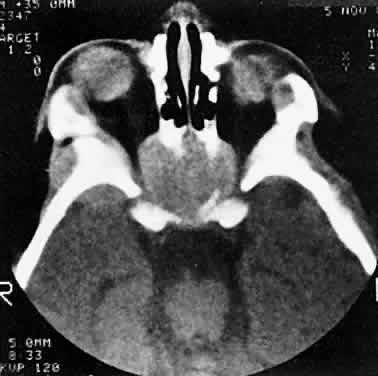

Within the orbit, rhabdomyosarcoma occurs most often, but not exclusively, in the superior nasal quadrant, with downward and outward displacement of the globe. CT scans show the topography of the orbital mass (Fig. 1A), as well as the possible extension into adjacent bone, paranasal sinuses, or the intracranial cavity. The circumscription that may be noted on CT is relative, because the lesion is not encapsulated and microscopically infiltrates normal tissue. Echography shows internal echoes of low-to-medium amplitude. Because the cellular tumor absorbs acoustic energy, the amplitude of the spikes falls off somewhat through the lesion (see Fig. 1B and C). MRI can help define the tumor's relationship to extraocular muscles (Fig. 2).

Fig. 2. MRI shows an intraconal tumor of lower intensity than the medial rectus muscle. The proximal muscle is splayed rather than compressed, suggesting that the lesion originated within the medial rectus. The diagnosis was alveolar rhabdomyosarcoma.